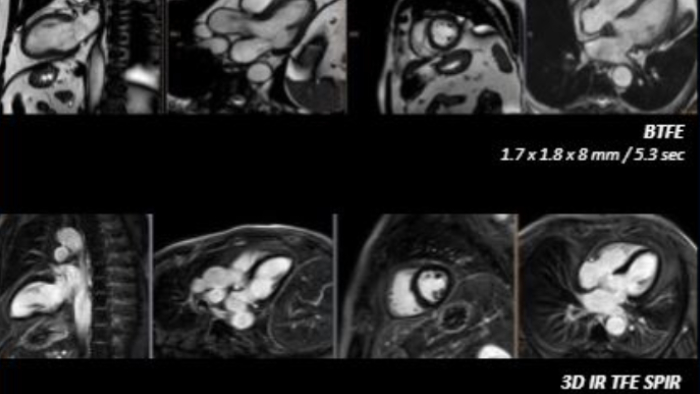

MR – Ingenia Ambition

Realize the potential of MR throughout the pathway with ultrafast exams, enhanced workflow, high-quality diagnostic imaging and enhanced patient comfort.